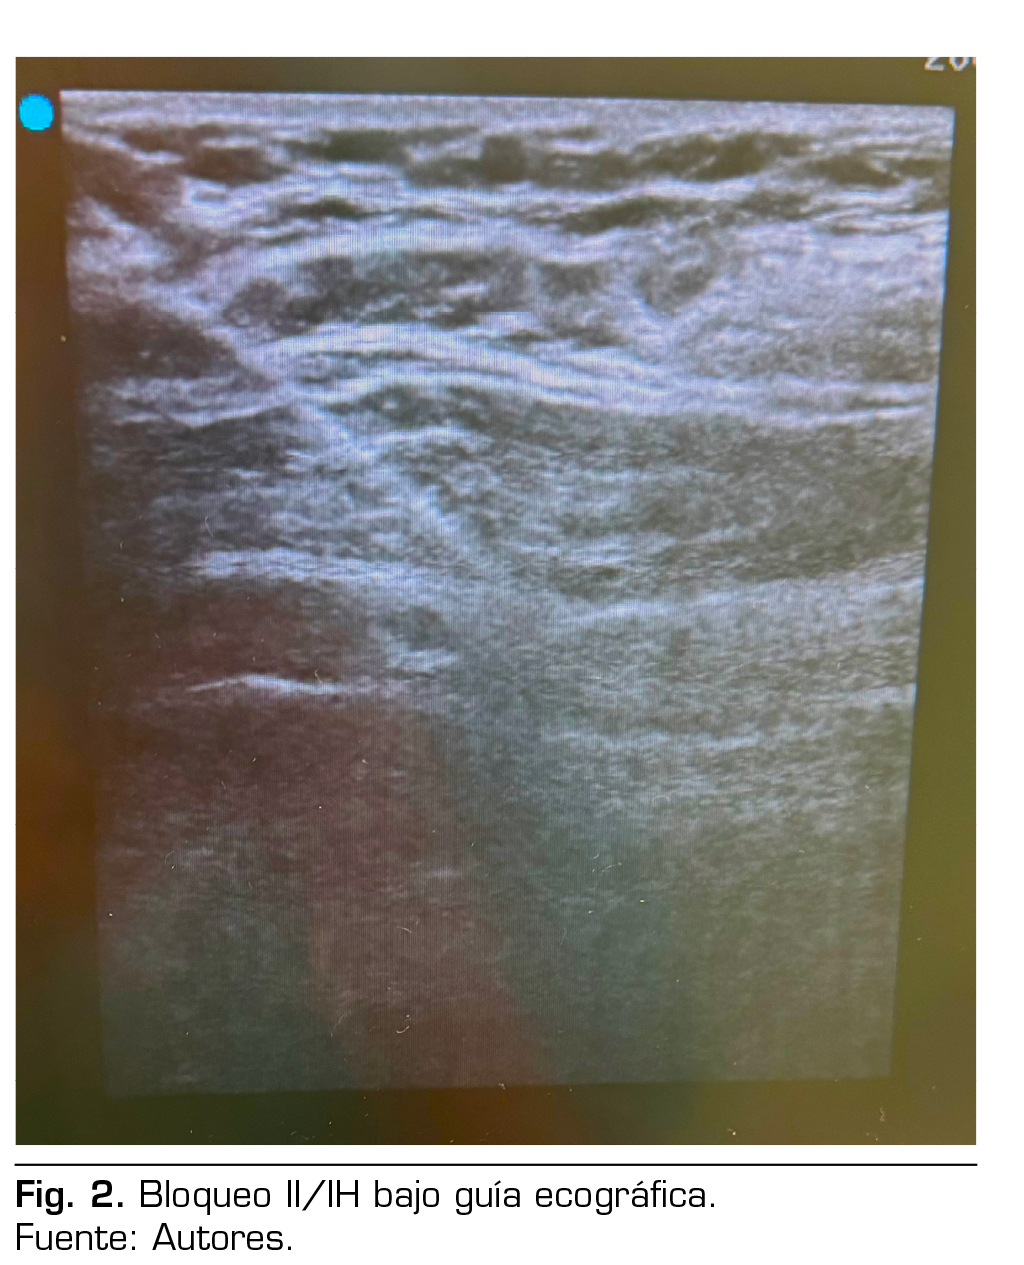

Presentamos el caso de una paciente de 88 años con diagnóstico de hernia inguinal izquierda que fue programada para hernioplastia electiva por cirugía ambulatoria en un hospital de día. En el estudio preanestésico se recoge que tiene antecedentes médicos de: hipertensión arterial controlada, fibrilación auricular en tratamiento con apixabán e insuficiencia cardiaca crónica compensada NYHA II, enfermedad pulmonar obstructiva con uso de oxígeno domiciliario nocturno, y no tiene antecedentes tromboembólicos; como antecedentes quirúrgicos: corrección de hernia discal a nivel de L5-S1 hace aproximadamente 20 años. Otros antecedentes de interés son los siguientes: cifoescoliosis moderada–severa, en imágenes diagnósticas como la radiografía de tórax anteroposterior, se observa cifoescoliosis severa y desplazamiento de mediastino a predominio derecho, como se muestra en la Figura 1; tiene un control ecocardiográfico que concluye función sistólica conservada, hipertrofia de ventrículo izquierdo, insuficiencia-estenosis aórtica severa, insuficiencia mitral moderada, insuficiencia tricuspídea severa, hipertensión pulmonar severa y dilatación moderada de aurícula izquierda. En el examen físico se confirma la cifoescoliosis dorsolumbar moderada-severa; en la evaluación de la vía aérea, se observa que tiene Mallampati 1, sin criterios de vía aérea difícil; analítica preoperatoria sin alteraciones de interés, paciente ASA III.